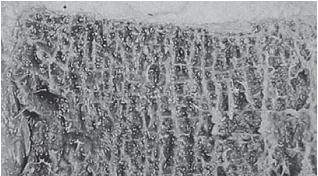

Таким образом, мы вкратце рассмотрели отделы позвоночного столба — этой удивительной конструкции, которая оптимально приспособлена для вертикального положения тела, работает чётко и слаженно. Но это, так сказать, обзор в целом. Теперь хотелось бы обратить ваше внимание на любопытные подробности из той же области остеологии (учение о костях), касательно важных элементов опорно-двигательного аппарата. Позвоночник человека — орган сегментарный (слово «сегмент» произошло от латинского слова segmentum — «отрезок»). Он состоит из отдельных позвонков, расположенных между ними межпозвонковых дисков, а также связок, суставов. Позвонок Итак, одним из основных элементов позвоночника является позвонок (vertebra). По своему строению типичный позвонок напоминает костяной перстень, состоящий из массивного тела позвонка (в нашем случае имитирующий большой драгоценный камень в этом кольце), дуги (точнее двух полудужек, соединяющихся сзади и образующих остистый отросток), замыкающей позвоночное отверстие. Данные отверстия, соединяясь, образуют позвоночный канал, где располагается спинной мозг. На дуге «кольца» имеется 7 по-своему интересных, анатомически выразительных отростков: это остистый отросток, два поперечных и четыре суставных отростка (два верхних и два нижних). В эту схему не вписываются только два верхних шейных позвонка (атлант и эпистрофей), крестцовые позвонки (из-за слияния в единую кость, их видоизменение) и рудиментарные копчиковые позвонки, которые, как мы уже выяснили, из-за особенностей отличаются своим строением от описанной схемы. У основания дуги имеется верхняя и нижняя позвоночные вырезки, которые при соответствующем соединении двух соседних позвонков образуют межпозвонковые отверстия. Тела позвонков приспособлены к тому, чтобы нести на себе тяжесть туловища, и являются основными опорными структурами позвоночника. ![]() Рисунок № 15. Образное сравнение позвонка и перстня Не случайно я сравнил тело позвонка с драгоценным камнем. Это действительно драгоценный по функциям элемент позвонка. Дело в том, что тело позвонка состоит из губчатого вещества пористой структуры, которое образовано отдельными костными перекладинами — трабекулами (лат. trabecula — небольшая балка, перекладина), основой микроскопичного строения которых являются костные пластинки. Ячейки губчатого вещества тела позвонка заполнены красным костным мозгом. А красный костный мозг, как известно, это важнейший орган кроветворения и костеобразования, поскольку в его тканях находятся кроветворные элементы (стволовые клетки), клетки, разрушающие кость (остеокласты) и клетки, образующие кость (остеобласты). Ценность заключается в том, что именно от тела позвонка поступает регулярное и единственное питание для межпозвонкового диска через замыкательную (гиалиновую) пластинку, отделяющую губчатую кость тела позвонка от межпозвонкового диска. О питании межпозвонкового диска мы будем говорить ещё не раз, поскольку это является существенным моментом в понимании причин возникновения и развития многих заболеваний позвоночника. А пока хочу привести наиболее доходчивое сравнение. Жизненно важное питание, поступающее от тела позвонка, представляет собой для межпозвонкового диска практически то же, что, к примеру, в Великую Отечественную войну представляла собой «Дорога жизни» для жителей блокадного Ленинграда (ныне Санкт-Петербурга). Ладожское озеро было тогда, подобно замыкательной пластинке, единственной транспортной магистралью, через которую поступало продовольствие для города. Поскольку мы уж коснулись темы Великой Отечественной войны, то приведу и другое, на сей раз весьма печальное сопоставление. Общеизвестный факт, как в концентрационных лагерях во время войны людей заставляли тяжело работать и при этом плохо кормили, вследствие чего доводили их до полного истощения, результатом которого зачастую была смерть. Аналогичный процесс происходит и в межпозвонковом диске. То есть, клеточки межпозвонкового диска, систематически испытывая значительные нагрузки и при этом не получая должного питания (а это происходит, к примеру, когда человек много сидит и мало ходит), истощаются и умирают, что соответственно со временем сказывается на диске в целом. ![]() Фото № 2. Наблюдается пористая структура тела позвонка в разрезе Но вернёмся к нашему перстню. О «драгоценном камне» — теле позвонка — у нас уже есть общее представление. Теперь полюбуемся отростками, расположенными на дуге. Поговорим о четырёх суставных отростках позвонка (двух верхних и двух нижних), за счёт которых позвонки соединяются с выше - и нижележащими позвонками. Кстати, соединяясь, нижние суставные отростки вышележащего позвонка и верхние суставные отростки нижележащего позвонка образуют дугоотростчатые суставы, так называемые истинные синовиальные суставы. Как вы знаете, суставом как таковым, именуют подвижное соединение костей скелета (позволяющее им перемещаться друг относительно друга), принимающее участие в осуществлении опорной и двигательной функций. Наряду с истинными суставами имеются полусуставы (по-научному межпозвонковые симфизы; symphysis — «переходные соединения»), к которым относятся и межпозвонковые диски. МРТ № 4 ![]() МРТ № 5 ![]() На МРТ № 4 наблюдается межпозвонковый диск в начальной стадии развития дегенеративно-дистрофического процесса. На МРТ № 5 наблюдается межпозвонковый диск на более поздней стадии развития дегенеративно-дистрофического процесса. ![]() Фото № 3. На фото макета позвоночника стрелкой указан дугоотростчатый сустав позвоночника. Дугоотростчатые суставы имеют синовиальную оболочку, фиброзную капсулу, суставную полость с синовиальной жидкостью, связки. Каждый дугоотростчатый сустав покрыт гиалиновым хрящом, по краю которого (на расстоянии 2–4 мм от края сочленяющихся поверхностей) прикрепляется капсула сустава. Изнутри суставная капсула покрыта синовиальной оболочкой. По передней поверхности она покрыта желтой связкой и составляет заднюю поверхность межпозвонкового отверстия. Капсула усиливается дорсально за счёт многораздельных мышц и вентрально жёлтой связкой, которая вплетается в неё в верхнемедиальном отделе. Верхний суставной отросток лежащего ниже позвонка массивнее нижнего и расположен больше кпереди и кнаружи, а нижний — кзади и кнутри. Часть верхнего суставного отростка у корня дуги участвует в формировании бокового углубления позвоночного канала. |